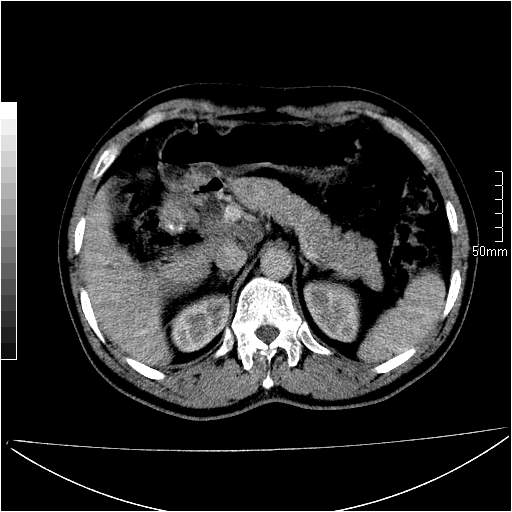

男性,54岁,皮肤黄染,搔痒一周余.b超示肝左叶回声异常.初步诊断1胆总管下段结石2胆囊结石伴慢性胆囊炎请各位战友帮忙看一下肝脏多发低密度如何解释恰当.增强效果不是很好.请大家见谅.

首先,胆总管下端结石梗阻伴肝内胆管扩张可确定。

另外,肝八段低密度占位,呈多灶性,考虑肝脓肿或肝癌可能,(图像质量欠佳)建议进一步检查。

既然做了增强,为什么光提供延时期片子,肝动静脉期肝右叶前下段病灶增强如何?另外胆囊壁增厚,欠规整,内密度不均,与肝右叶病灶分界不清,增强表现怎样?肝内胆管轻度扩张,胆总管扩张,但未见明显结石影,也应提供增强早期图像才好鉴别扩张原因。片子较清,但不够完整,暂考虑1.胆囊癌肝局部浸润,或肝癌胆囊侵犯,2.胆总管下端或胰头钩突部占位。总之本人看不明白,请高手画图指示,先谢了!

由于胆囊窝内结构显示不清,肝脏病灶又邻近胆囊窝首先考虑胆囊癌肝受侵犯。而后因肝脏病灶强化有渐进改变,且相邻胆管扩张,故考虑肝胆管细胞癌待排。

左肝胆管细胞癌。

胆总管下端结石。